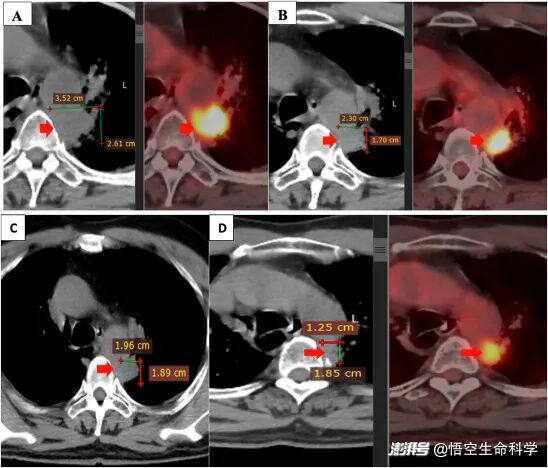

▲原發(fā)腫瘤在聯(lián)合治療前后。

從結(jié)果看,這位患者在4.5個月內(nèi)完成6次回輸后,病灶體積減少約 50%,疼痛癥狀完全緩解,且未報告明顯治療相關(guān)毒性。這些變化很難簡單歸因于某一個單獨因素,更像是多重機(jī)制共同作用后的結(jié)果。

它并不能被理解為“NK 細(xì)胞治好了癌癥”,但提供了一個清晰信號:當(dāng)免疫治療進(jìn)入平臺期時,問題可能并不完全出在免疫細(xì)胞本身,而是出在它們所處的戰(zhàn)場環(huán)境。這類病例的價值,正是在于幫助研究者和臨床醫(yī)生更精確地拆解“免疫失敗”的真實原因。